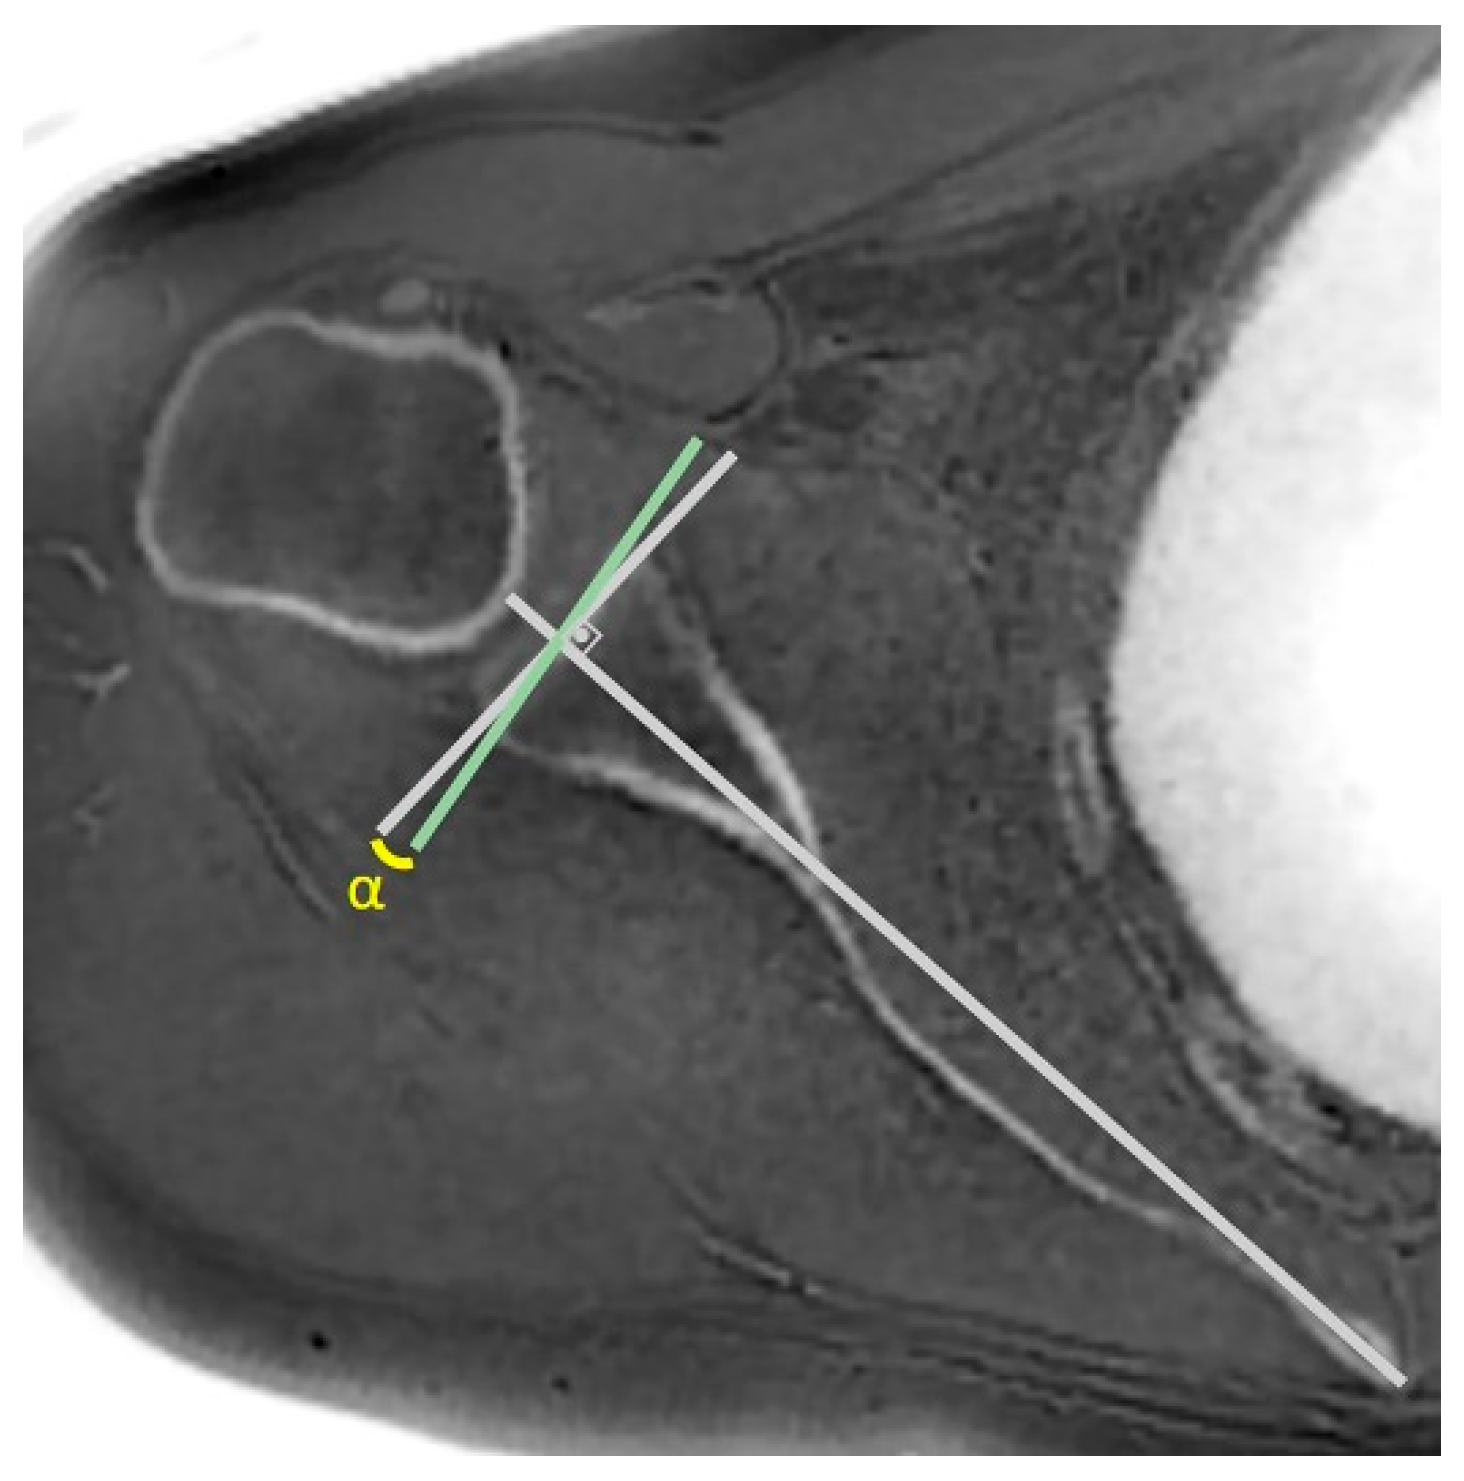

- MRI-based measurements